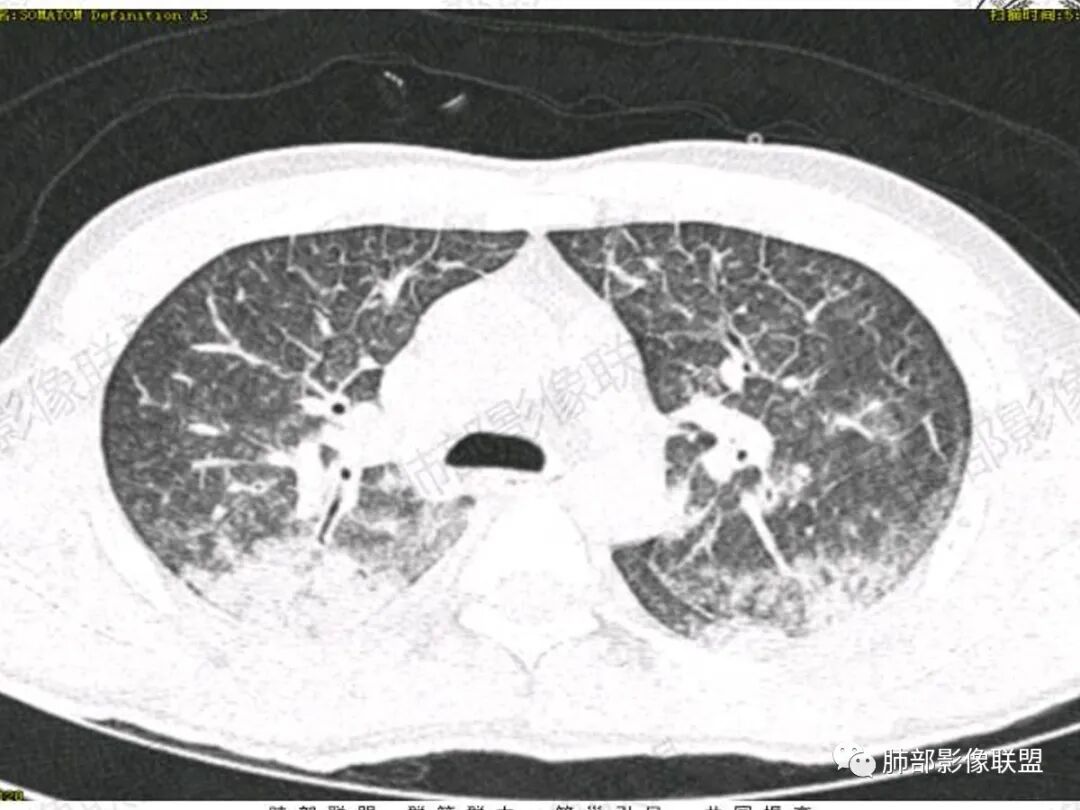

双肺上叶,下叶背段多发斑片状实变影,以胸膜下分布为主,部分重力作用,以背侧为主,部分小叶间质增厚,部分周围伴有散在磨玻璃影,边界欠清,临床急性病程,血象增及PCT明显增高,意识模糊,考虑:吸入性肺炎?鉴别:AHP?CEP?PCP

37岁男性 气促 两肺对称分布磨玻璃及小叶间隔增厚,两肺上叶后段及下叶背段为著,有重力分布,下部密度较高,请结合病史排查肺水肿,理化性肺泡损伤

双肺叶透亮度对称性减低,呈磨砂状,小叶间隔规则增厚,上叶为甚,左右肺叶中轴间质增厚(示淋巴回流障碍),双肺叶弥散磨GGO征,以肺腺泡分布,双肺上,下叶融合片状,有重力分布特点,心脏大,肺动脉干增粗,首选心源性肺水肿,但无胸腔积液。与急性肺损伤和ARDS鉴别

影像:两肺上叶小叶间隔增厚,斑片,腺泡结节,重力分布,下肺不累及

影像学提示肺水肿与肺泡腔液性渗出(小叶间隔增厚+实变+重力趋势),上叶显著。

双肺弥漫性病变以上肺,向心性,背部分布为主,肺动脉干无增粗,急性起病,典型的吸入性肺炎。

青年男性,气促7小时入院,意识模糊,白细胞及中性粒明显增高,PCT增高,CRP不高,心率快,体温正常,血压正常。胸部CT:双肺上叶小叶间隔光滑增厚,中轴间质增厚,弥漫性磨玻璃、多发斑片影,以上肺、背侧分布为主。影像表现考虑为肺水肿。病因:病史不支持肾功能衰竭、心源性、高原性肺水肿,无发热,似乎也不支持细菌、病毒、真菌等感染引起。吸入毒物?吸入水?

病灶的分布以上肺为主

确实要考虑吸入,倾向于吸入的是气体类的可能,因为朝上走

结合病史,最终诊断是 “急性烟雾吸入性肺损伤”,影像学表现主要是肺水肿及弥漫性肺泡损伤改变,因为烟雾气体吸入肺内分布以上肺显著,因此影像学表现也是累及上肺更明显。损伤因素包括大量一氧化碳 二氧化碳 一氧化氮等燃烧产生的有毒气体,也有烟雾粉尘颗粒对气道黏膜的损伤。